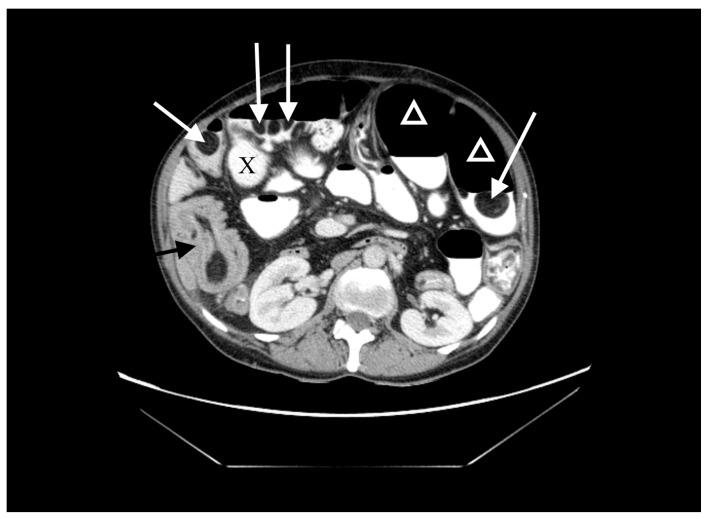

空肠憩室病和空肠脂肪瘤病是罕见病症。通常无症状,但在某些情况下可能引发严重并发症。肠套叠在成年人中并不常见,但如果能迅速诊断,可通过手术治疗,通常预后良好。

我们报告一例60岁女性患者,有慢性营养不良和贫血病史,主诉急性腹痛、呕吐和腹泻。腹部增强计算机断层扫描(CT)显示肠套叠、多个巨大空肠憩室和多个脂肪瘤。患者接受了紧急手术,但由于病情严重程度无法进行根治性治疗。一个月后,因脂肪瘤导致回肠造口梗阻,需要再次手术。患者因营养不良和并发的代谢紊乱病情恶化,最终死亡。